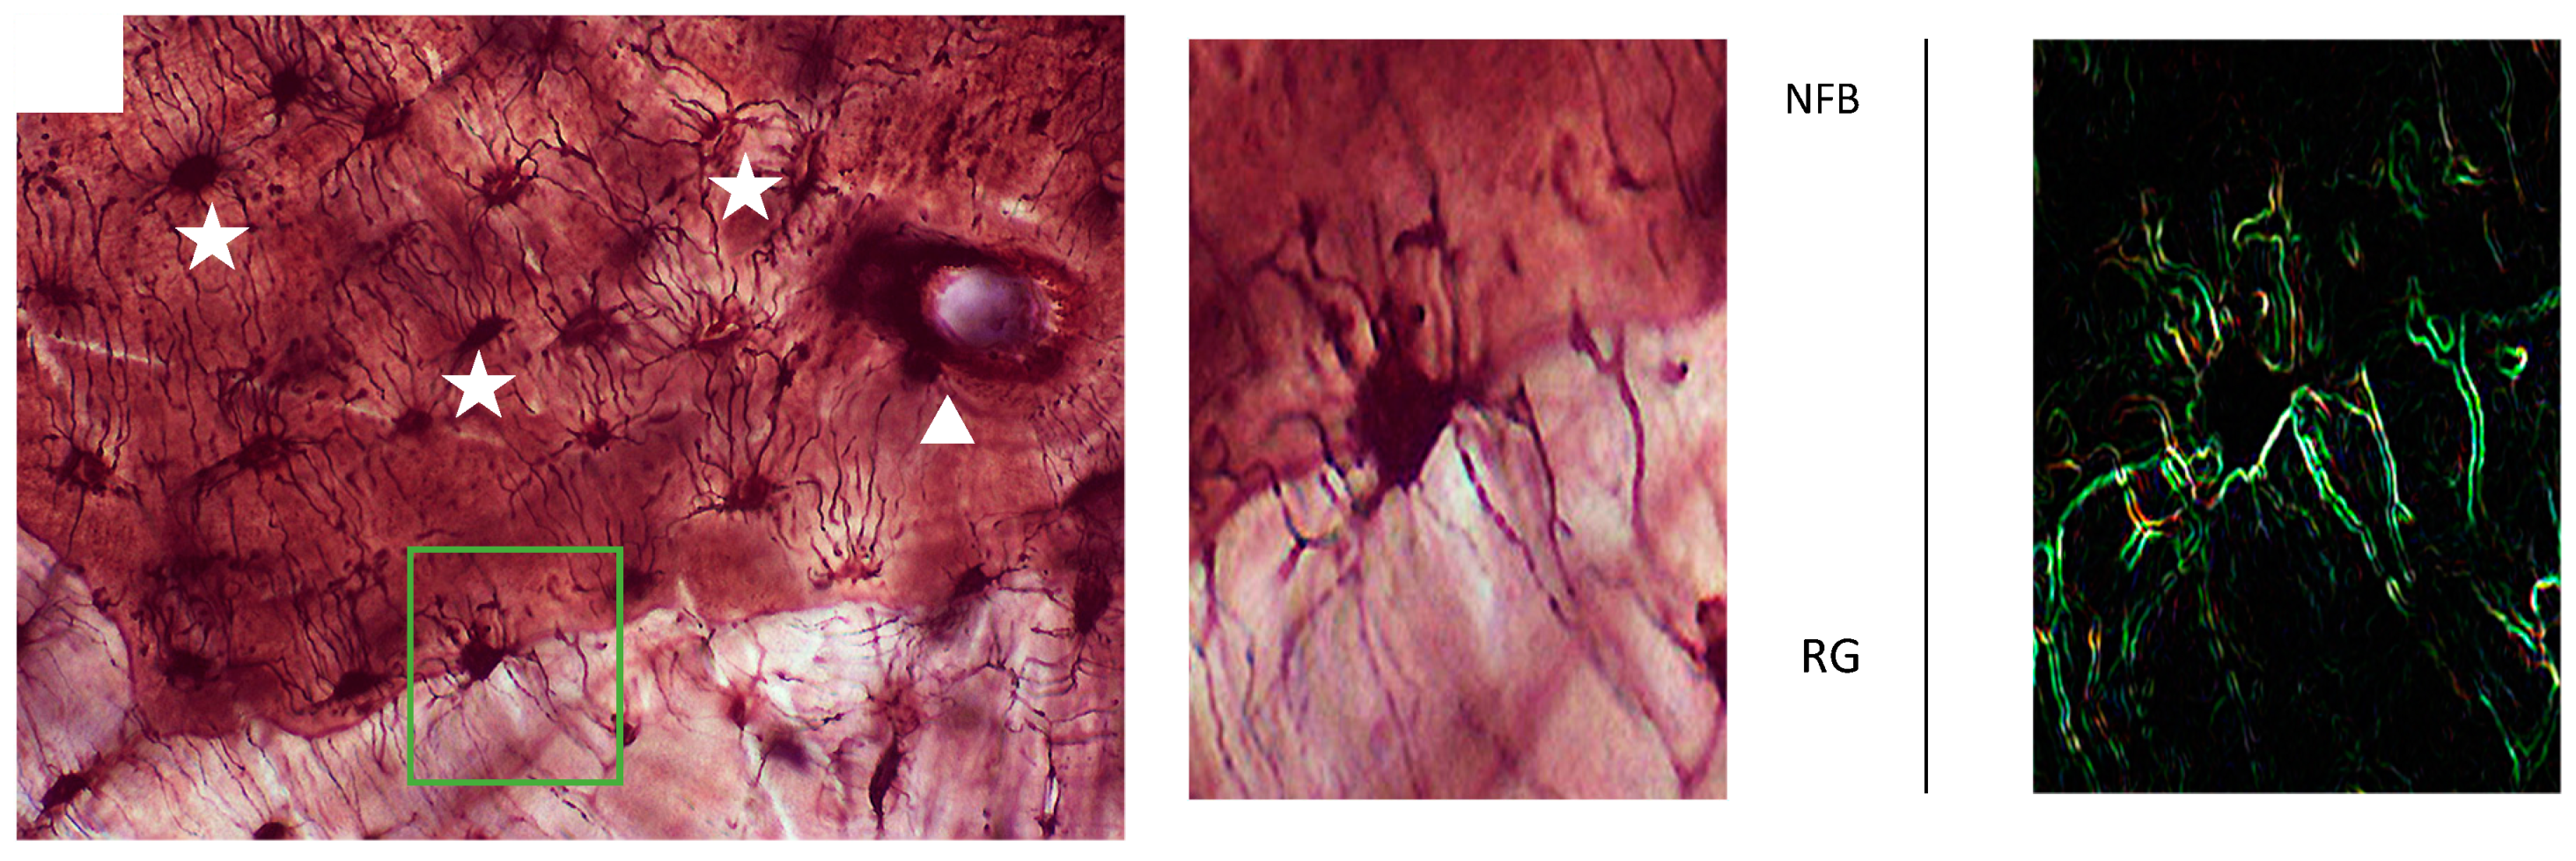

2.1. Specimen Processing and Histologic Analysis

2.2. Scanning Electron Microscopy (SEM)

3. Results